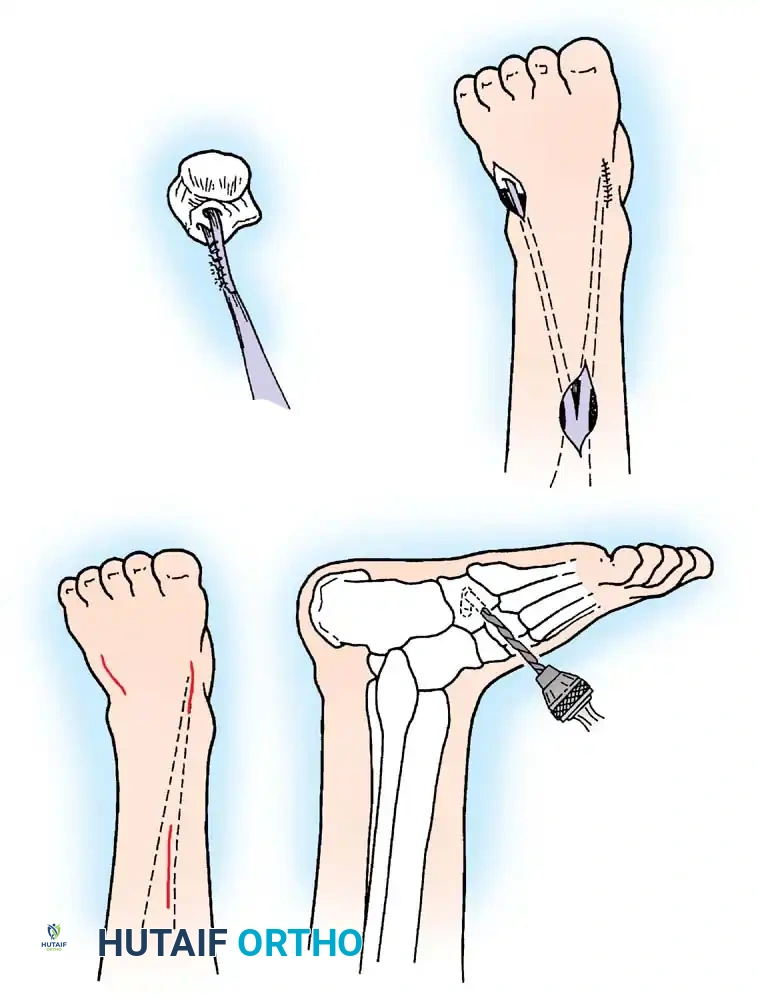

Loss of active elbow flexion prevents the patient from bringing the hand to the face. The Steindler flexorplasty is a classic and highly effective procedure.

Image

It involves proximal advancement of the flexor-pronator origin from the medial epicondyle to the anterior humerus. By increasing the moment arm of these muscles across the elbow joint, the patient can utilize wrist flexors to achieve active elbow flexion. Alternative options include transfer of the triceps, pectoralis major, or latissimus dorsi, depending on the availability of expendable donors.